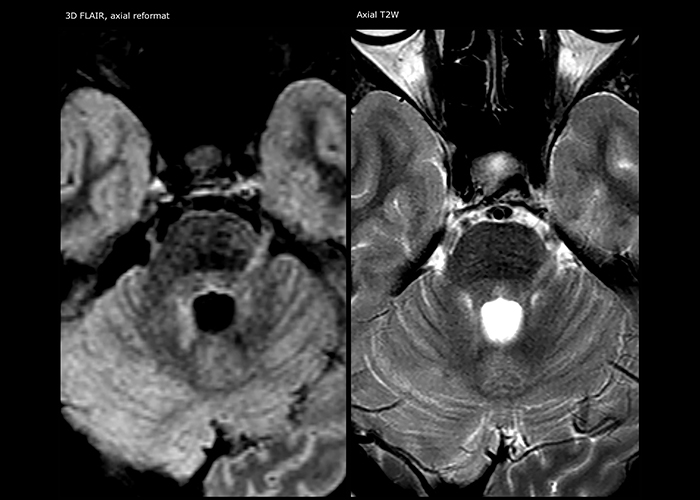

For MS imaging in the brain, Dr. Savatovsky uses 3D FLAIR as the basic sequence to visualize the lesions and assess the situation and lesion load. “We count the lesions in each location to determine if the criteria of the disease are fulfilled. We use a T2-weighted sequence because our neurologists are used to it. We compare the lesion load on FLAIR with a 3D T1 post-contrast sequence to help us determine whether lesions are old or new. We typically administer the contrast before the patient enters the machine because it shortens the examination time and allows to visualize active lesions that tend to be more visible after several minutes. When a differential diagnosis is difficult, we add sequences such as susceptibility imaging, because some focal MS lesions have a small vein in the center[3].”